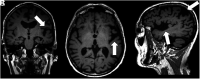

FIG 2.

Coronal T1-weighted MR imaging (A), axial T1-weighted MR imaging (B), and sagittal T1-weighted MR imaging (C) in a right-handed individual with impaired repetition of phrases demonstrate asymmetric widening of the left Sylvian fissure with left posterior peri-Sylvian and temporoparietal atrophy (white arrows, A–C), suspicious for lvPPA.